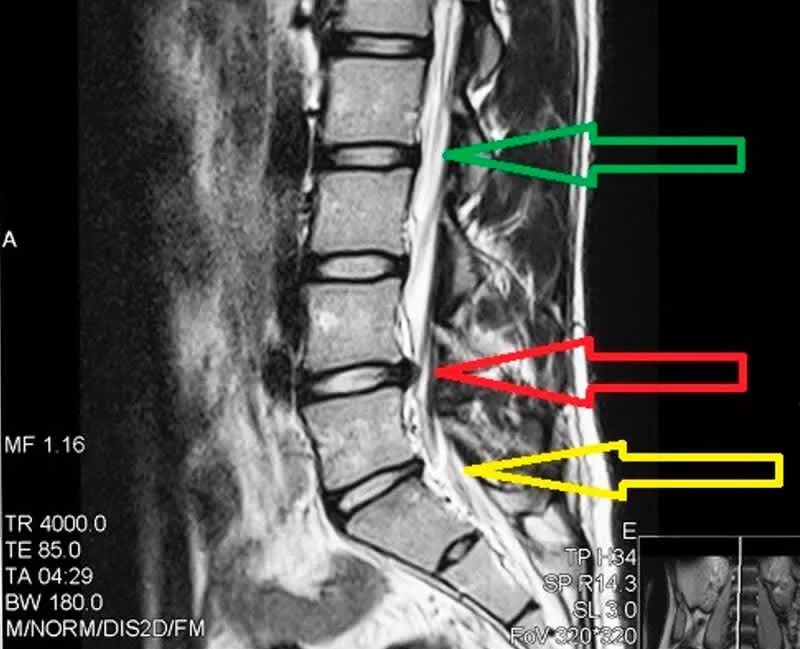

Диффузная грыжа l4 l5